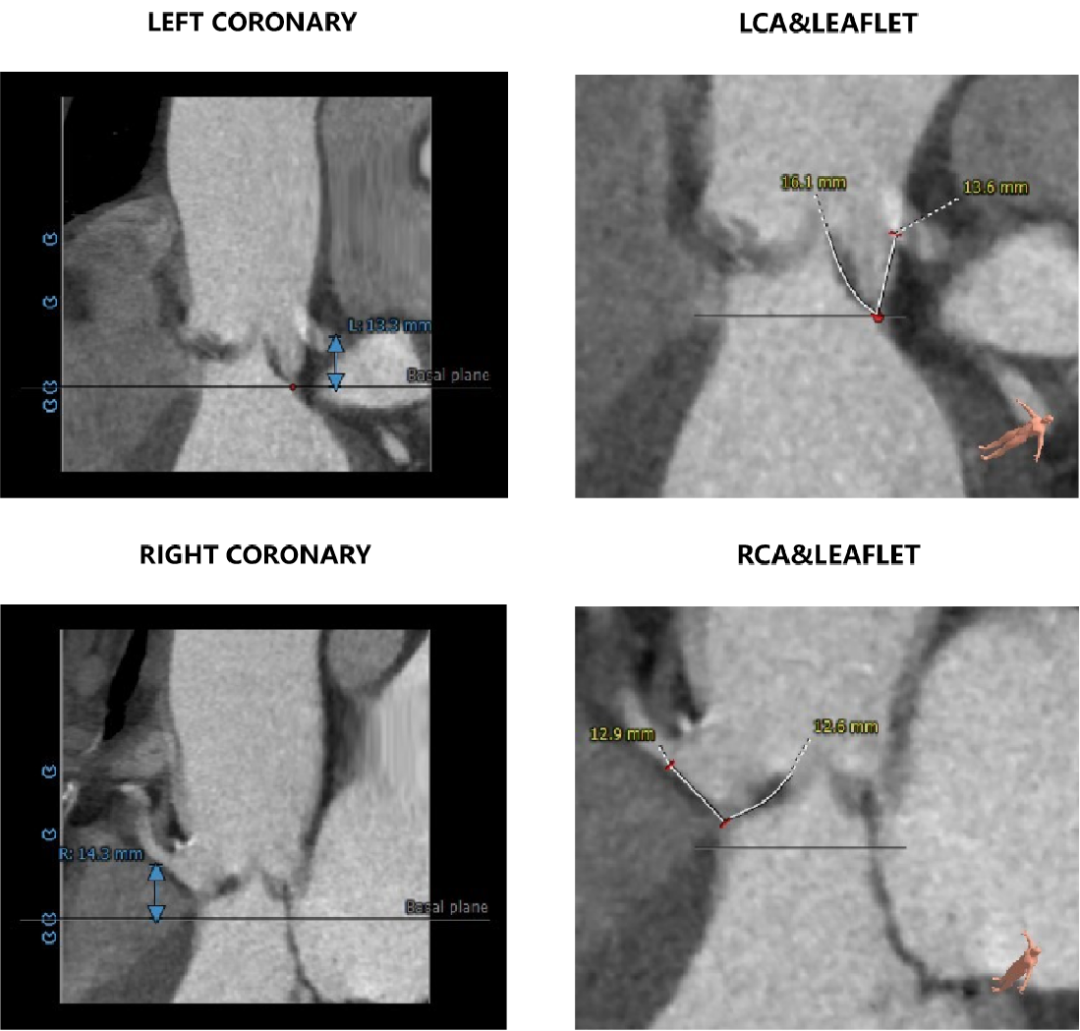

主动脉根部评估:

CT数据显示该患者为三叶三窦式主动脉瓣。

主动脉瓣瓣环周长81.5mm,平均周长径 26mm,SOV:31.8mm*31.5mm*29.6mm,瓣叶增厚,瓣上未见明显钙化,瓣环水平夹角58°。

左冠开口高度18.8mm,右冠开口高度21.9mm,高度可,根据瓦氏窦内径和瓣叶长度综合判断,冠脉堵塞风险小。

HU850钙化积分6mm³